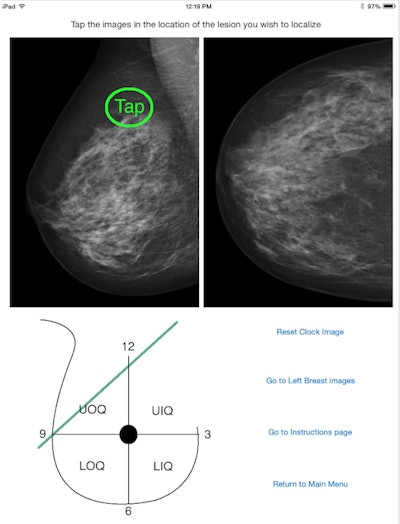

AuntMinnie.com presents the next article in an ongoing series highlighting notable mobile apps in radiology. In this installment, we take a look at Mammography Localizer, an iOS app designed to help users learn how to localize breast lesions. The app shows lesions on standard screening mediolateral-oblique (MLO) and craniocaudal (CC) mammograms, along with their approximate corresponding location on a clockface schematic of the breast, according to developer Dr. John Bisges.

Bisges: I was inspired to create this app during a mammography rotation when I was having trouble telling which quadrant a breast mass was in from the standard CC and MLO views. Then I read a section on breast mass triangulation in Dr. Gilda Cardenosa's textbook Breast Imaging Companion, where she described a method of breast mass localization that was described to her by Dr. G.W. Eklund. I wondered if that method could be transformed into an application that I could use to double-check my work and improve my performance on the rotation. It took some time and experimentation to create a working version, and with it my performance on subsequent mammography rotations improved.

It's a very simple -- and hopefully user-friendly -- app. I tried to keep it as uncomplicated as possible. My goal was to create a simple, free tool to address a very specific problem for radiology residents like myself.